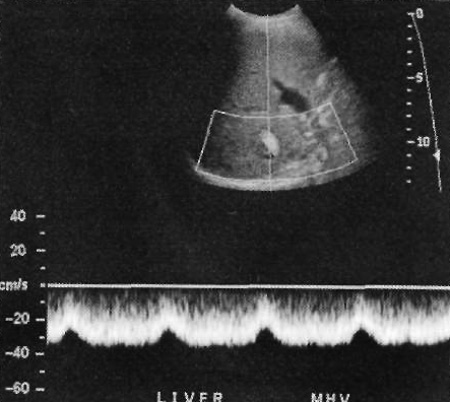

Низкое сопротивление (< 0,5) свидетельствует о шунтировании кровотока, тромбозе печеночной артерии или ее стенозе. Печеночный артериальный кровоток может повышаться при циррозе печени и некоторых опухолях (фото 1).

Фото 1. Спектральная допплерография печеночной артерии в норме. Индекс сопротивления – 0,64